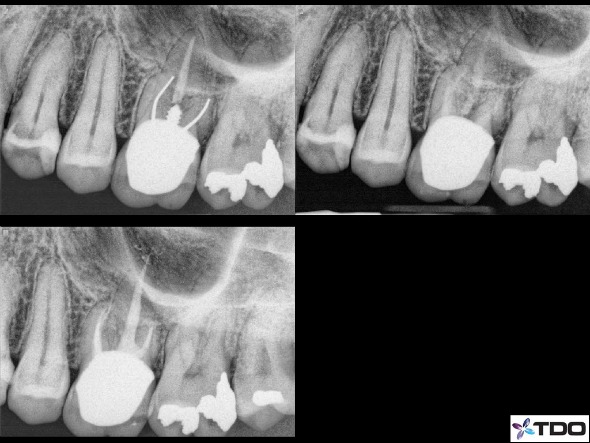

Another example would be in retreatment scenarios that have a post to remove. We would need to open larger coronally in order to gain access to the lateral sides of the post/cements/dentin to dislodge it (figure 5).

Figure 5: Here is a case in which the MB and DB canals had a silver point and the P canal had a wide post. I therefore needed to open the access larger in order to use the various instruments to retrieve the silver points and the post. Even though you cannot see the access size with the crown in place, this is a good example of a retreatment case that will require a larger coronal access. The radiograph in the upper right is with all materials removed and calcium hydroxide in place. The lower left if the immediate post-op x-ray.

A third reasonable common situation would be atypical anatomy of premolars such as multiple canals (figure 6).

Figure 6: Premolar tooth #21 with 3 canals. I had to access larger than usual in order to find the canals. A smaller access could have resulted in a missed canal that would lead to endodontic failure. The radiograph on the right is the 6 month recall showing excellent healing.